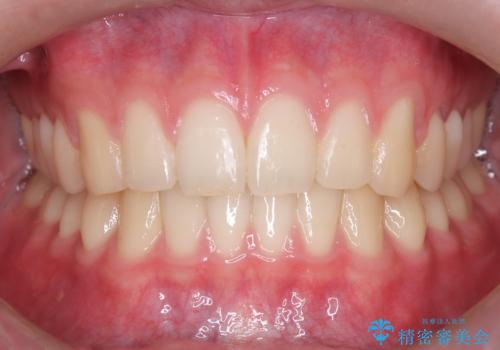

【ワイヤー矯正】すきっ歯を治したい

上顎中切歯間の隙間の他にもフロスが抵抗なく入るスペースが上顎は数か所ありました。スペースを閉じ下顎の歯列弓との調和をとるためIPRを行いました。

下顎の舌側傾斜気味の前歯も唇側へ歯軸傾斜させています。

矯正期間:1年2か月